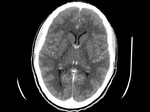

Kardio-CT

Mit Hilfe des neuen GE-Computertomographen ist es möglich, das komplette schlagende Herz im Bruchteil eines Herzschlages zu scannen und alle relevanten Gefäße darzustellen.

Im gleichen Arbeitsschritt ist es bei Bedarf möglich, eine Lungenembolie auszuschließen (bei einem Notfall).